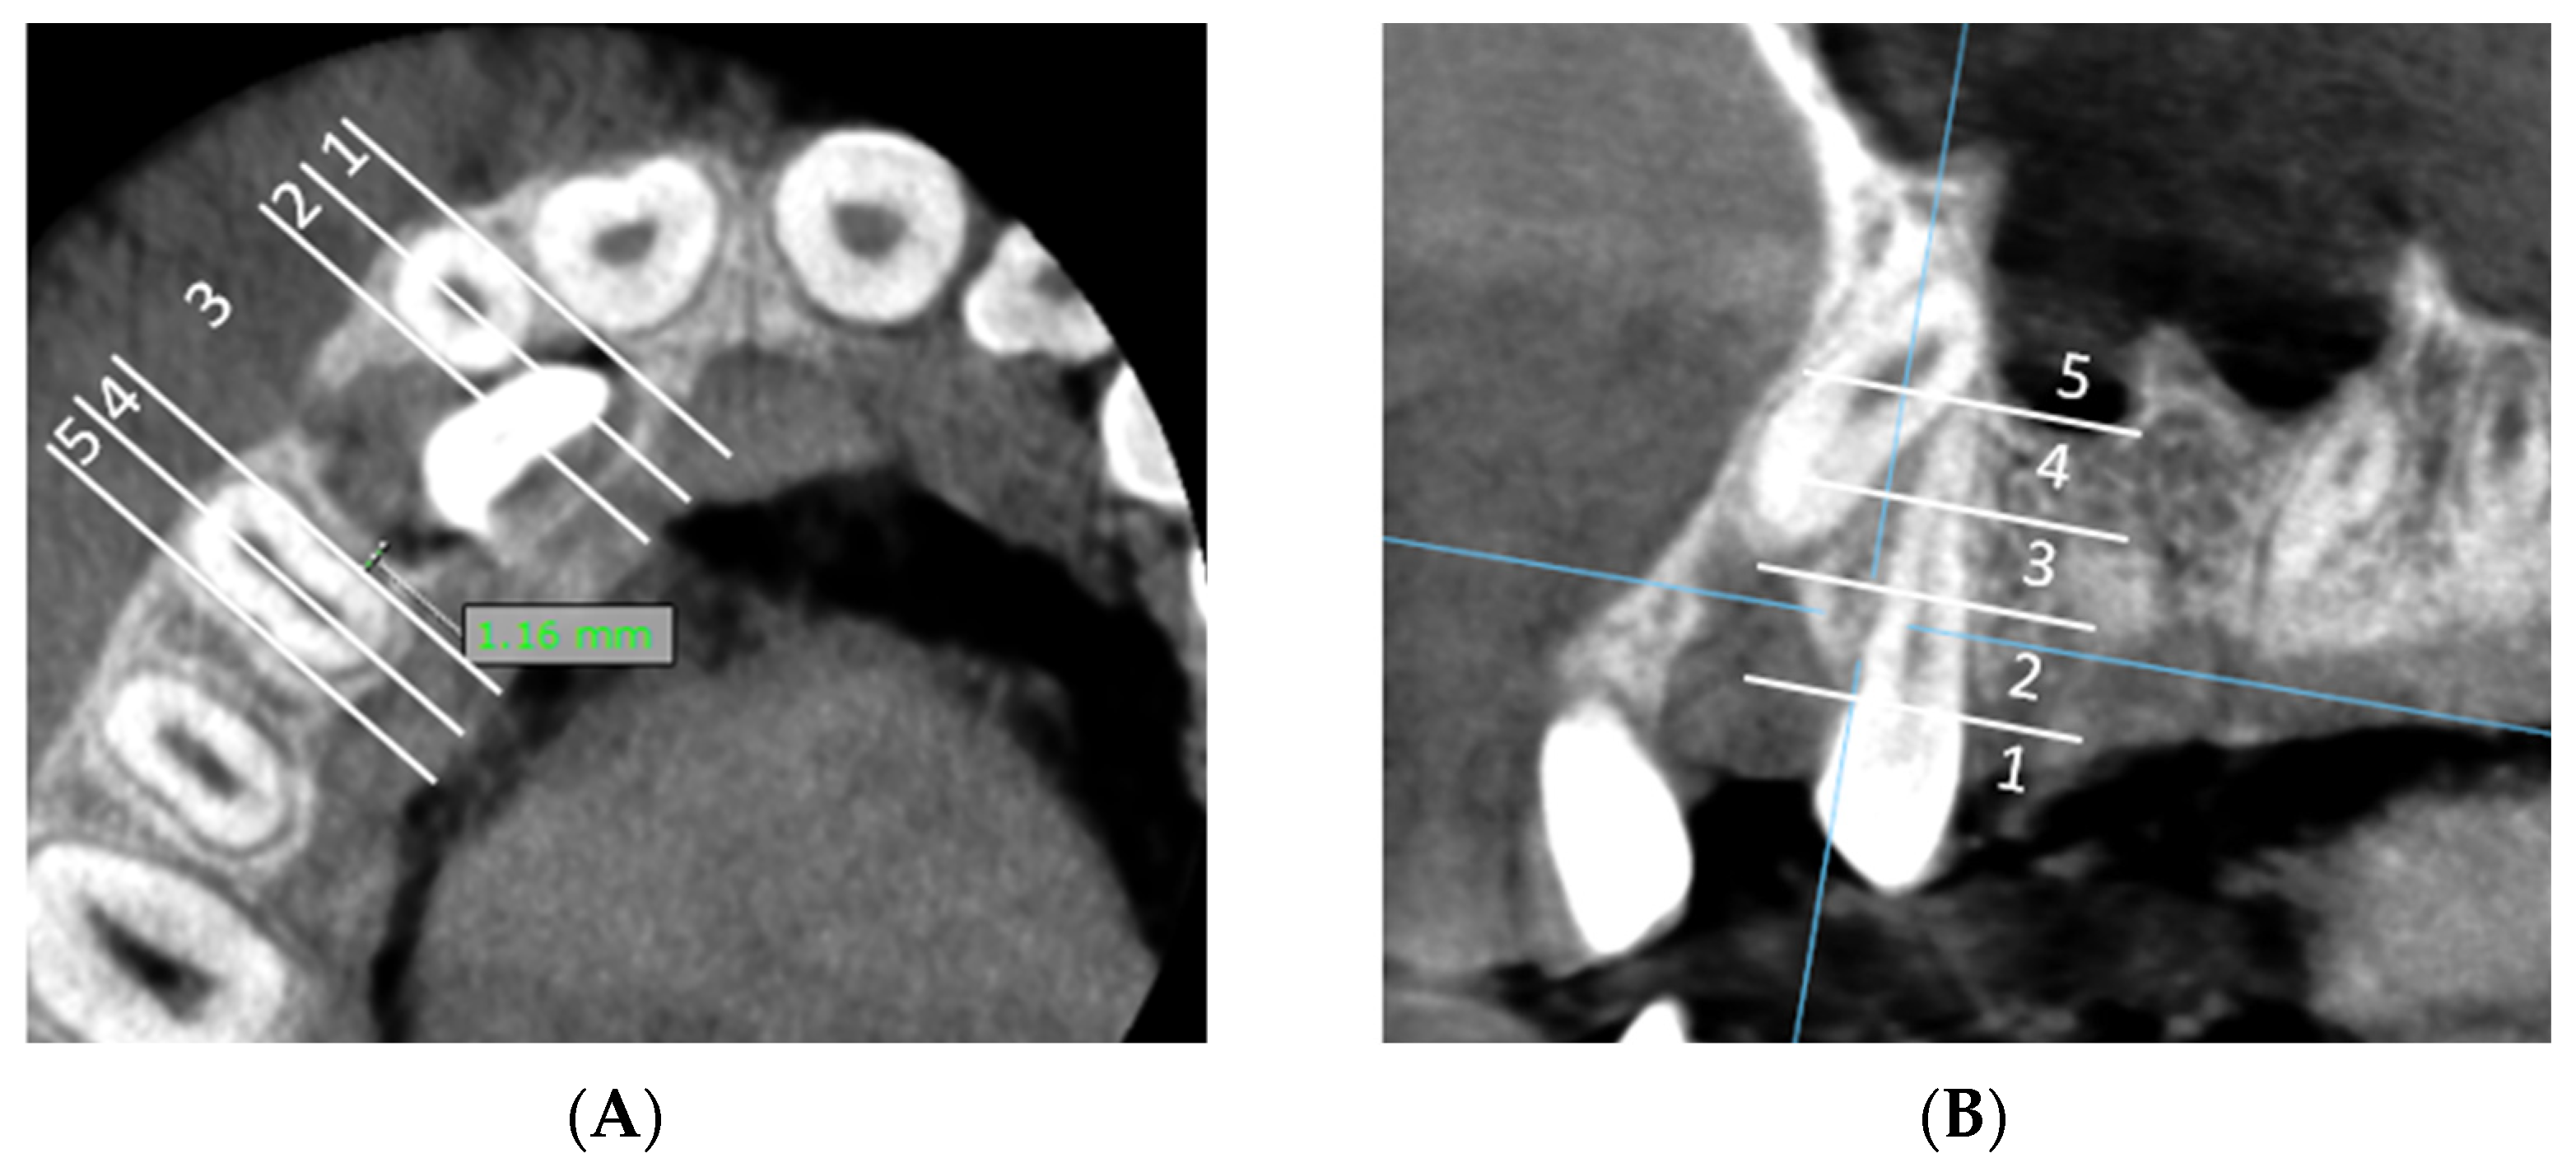

E: Measurement of the shortest distance between the dental follicle of the impacted canine and the lateral incisor/first premolar and assessment of horizontal and vertical zone of the canine follicle in relation to the lateral incisor/first premolar (Figure 3A,B).

Figure 3. (A) The minimal distance between the dental follicle of the impacted canine and the adjacent upper lateral incisor is 0 mm, indicating direct contact between the distal surface of the lateral incisor’s root and the dental follicle, and is classified in horizontal zone 2. The minimal distance between the dental follicle of the impacted canine and the adjacent first premolar is 1.16 mm and is classified in horizontal zone 3. (B) The shortest distance between the dental follicle of the impacted canine and first premolar is located in vertical impaction zone 2.

Dentistry 13 00497 g003